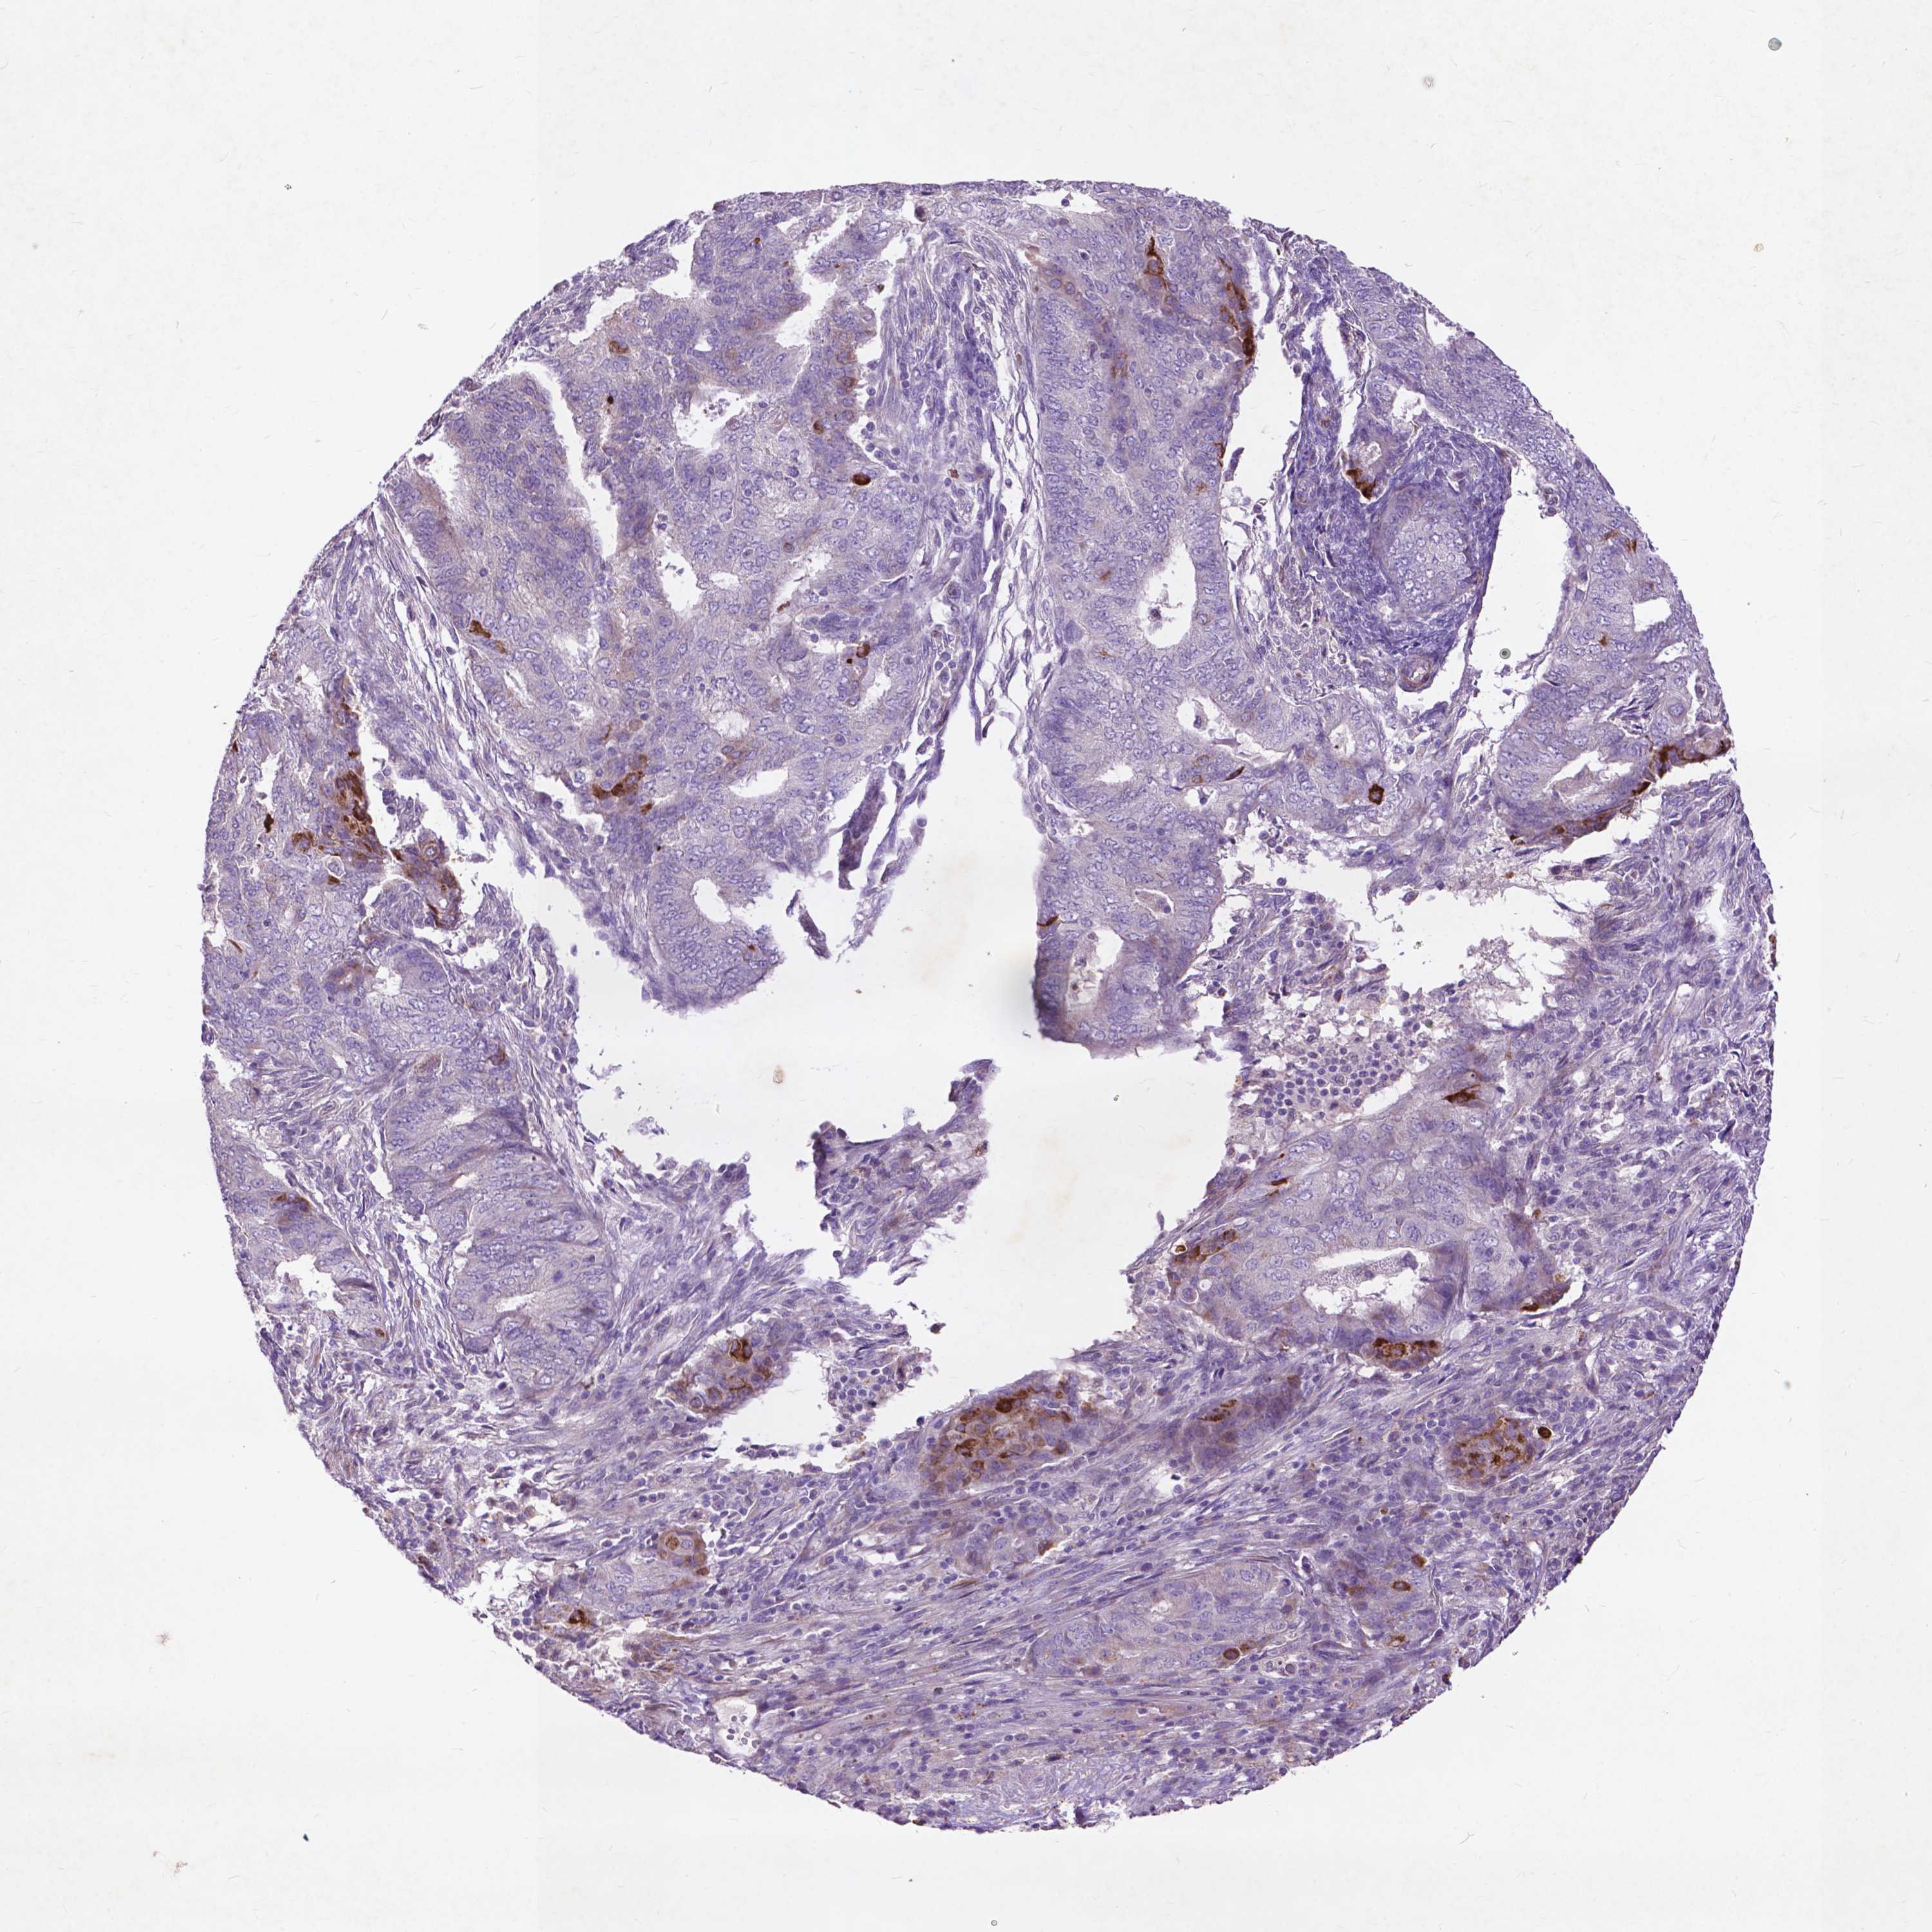

ENDOMETRIAL CANCER - Protein expressioni

A mouse-over function shows sample information and annotation data. Click on an image to view it in a full screen mode. Samples can be filtered based on level of antibody staining by selecting one or several of the following categories: high, medium, low and not detected. The assay and annotation is described here.

Note that samples used for immunohistochemistry by the Human Protein Atlas do not correspond to samples in the TCGA dataset.

Antibody stainingi

Antibody staining in the annotated cell types in the current human tissue is reported as not detected, low, medium, or high, based on conventional immunohistochemistry profiling in selected tissues. This score is based on the combination of the staining intensity and fraction of stained cells.

Each image is clickable and will lead to virtual microscopy that enables deeper exploration of all samples and also displays staining intensity scores, fraction scores and subcellular localization as well as patient and tissue information for each sample.

Antibody HPA068093

Staining

High

Medium

Low

Not detected

Intensity

Strong

Moderate

Weak

Negative

Quantity

>75%

75%-25%

<25%

None

Location

Nuclear

Cytoplasmic/membranous

Cytoplasmic/membranous,nuclear

Adenocarcinoma, NOS

Adenocarcinoma, metastatic, NOS